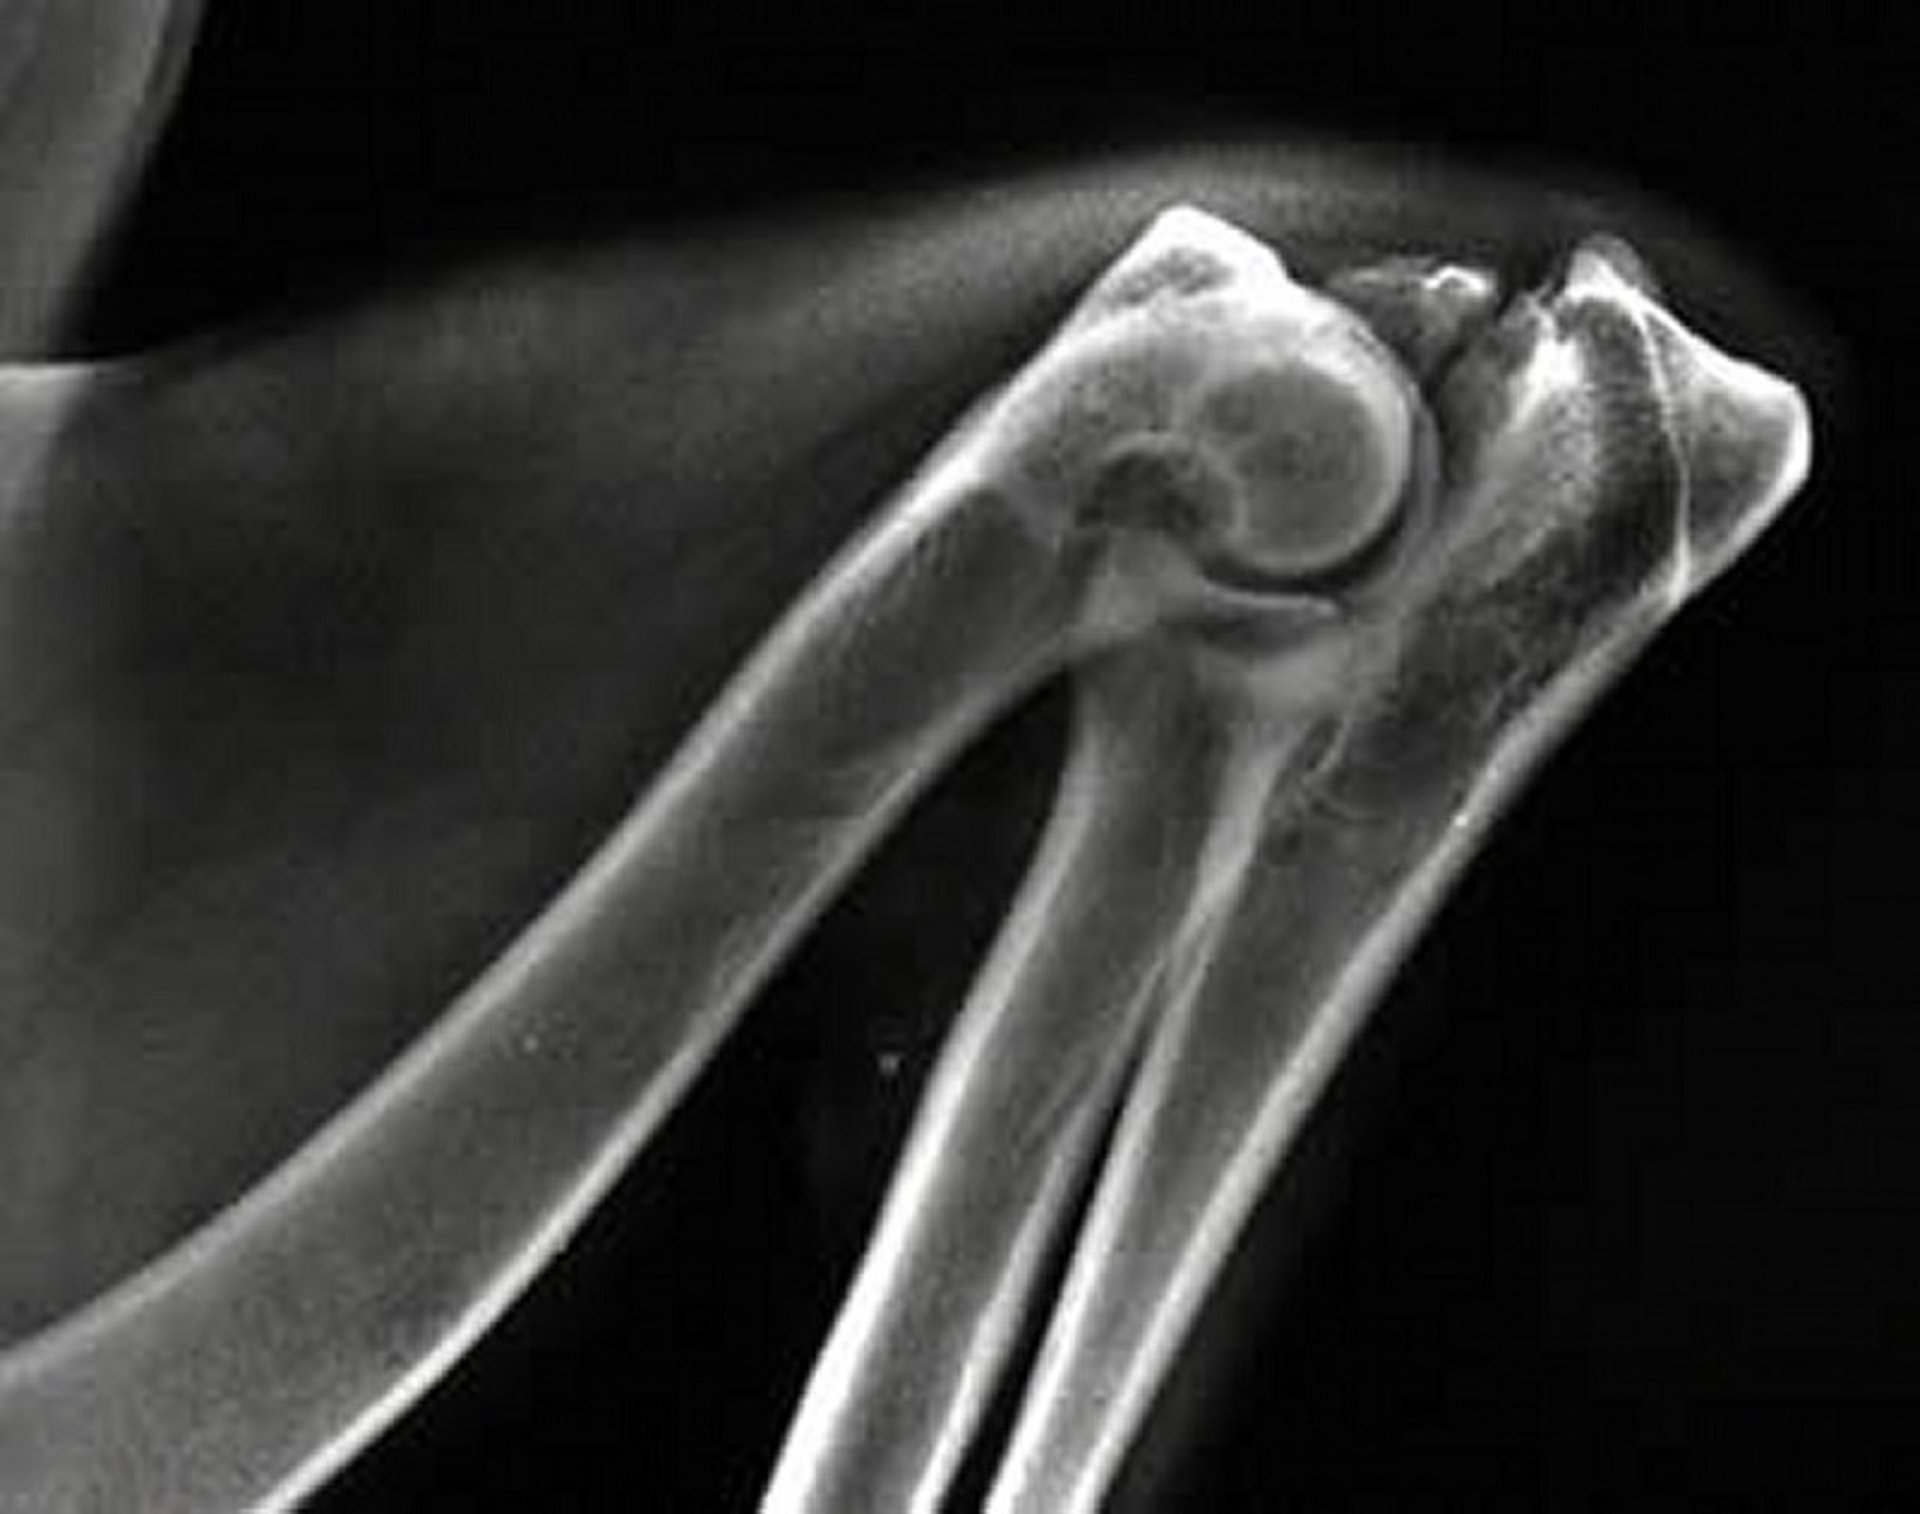

Ununited anconeal process, radiograph, dog

Mediolateral radiographic view of the fully flexed elbow joint of a dog with an ununited anconeal process, a component condition encompassed within elbow dysplasia. Note the separation or cleavage of the anconeal process from the proximal ulna.

Courtesy of Dr. Ronald Green.